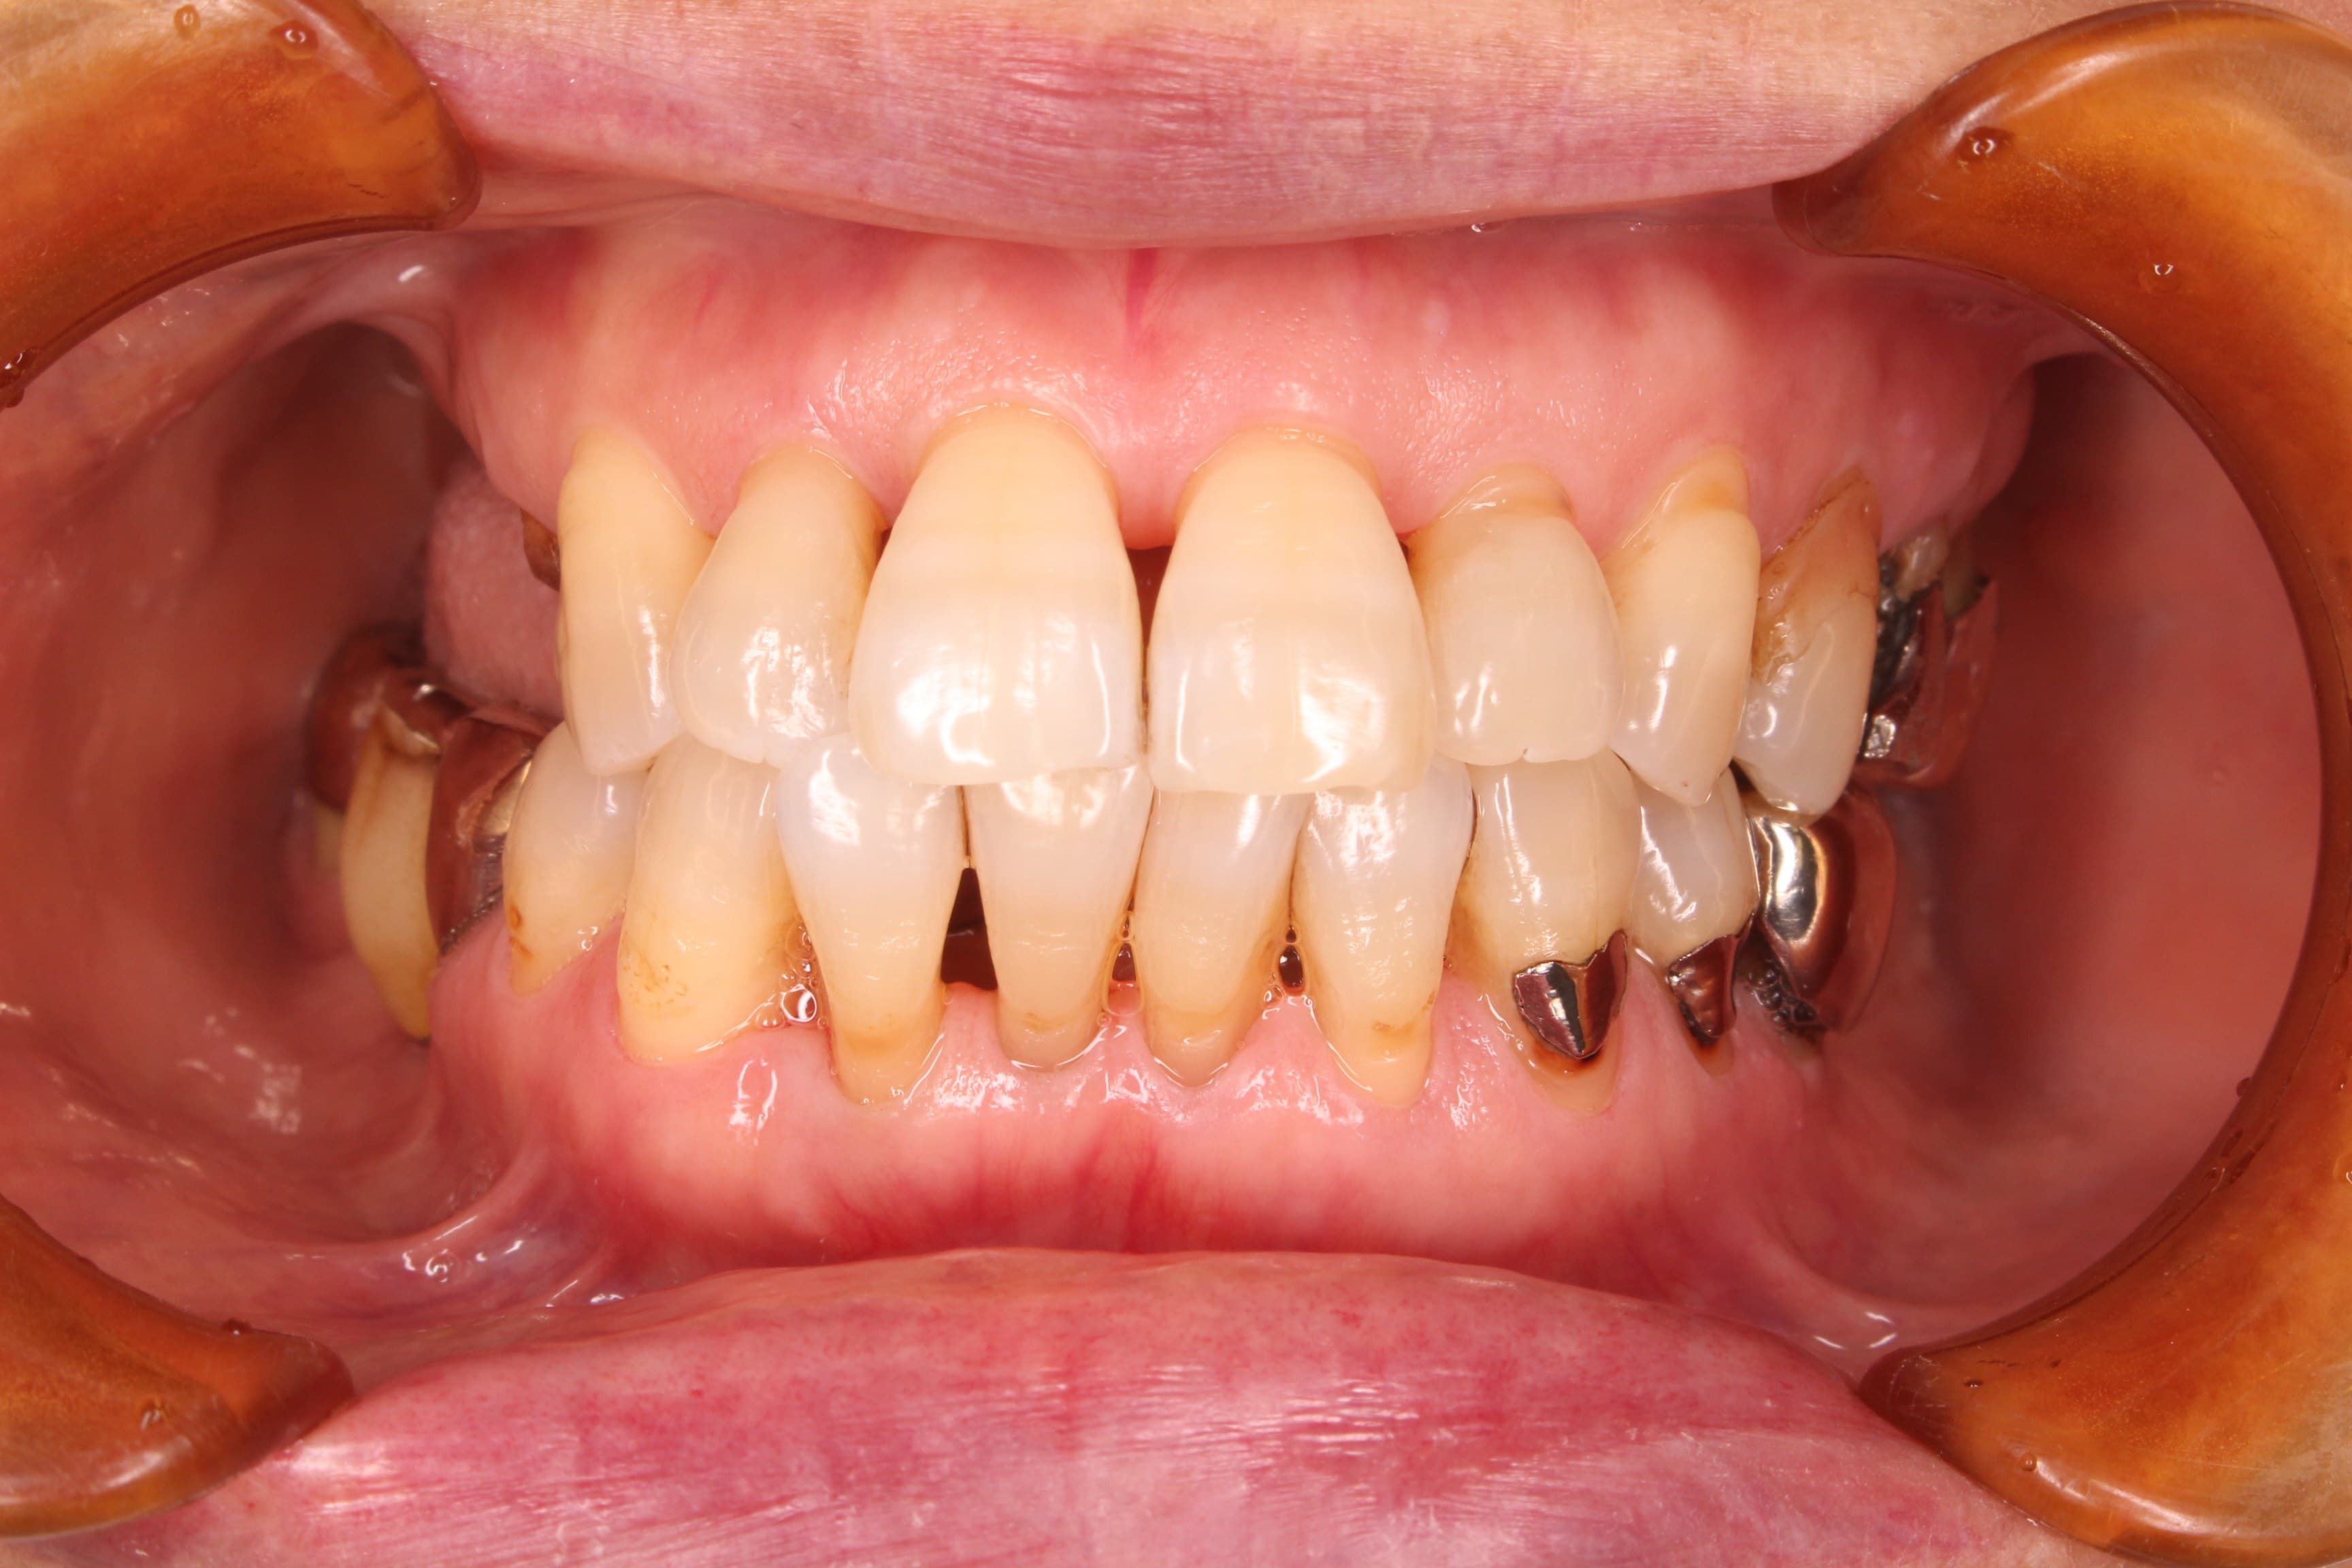

歯周治療終了後

※この後、折れた歯や虫歯、欠損部の治療を行っています。

高齢ではありますが、初めてのブラッシングトレーニングも、しっかりとご自身のペースで取り組み、磨いて欲しい所をしっかりと磨けるようになりました。

また、初診時とは健康に対する意識も大分変ったように思えます。

今回の治療をきっかけに、歯を残そうと思って頂けた事が、とても嬉しく思います。